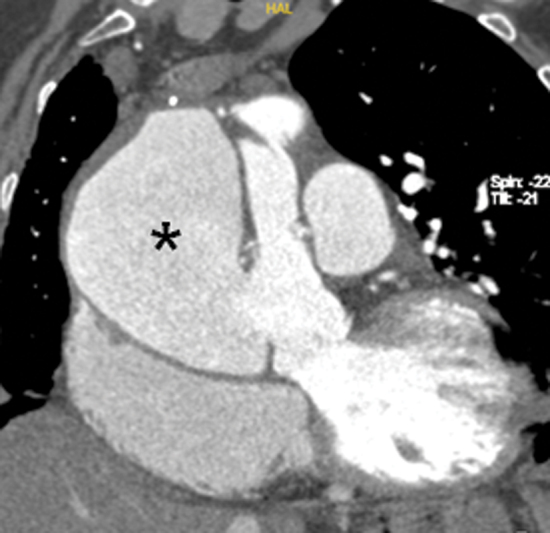

Aortic pseudoaneurysm occurs in 10 to 24% of patients after acute type A aortic dissection repair. We report the case of a 72-year-old female who developed an intraoperative iatrogenic ascending aortic dissection following mitral valve repair. A giant ascending aortic pseudoaneurysm was detected on follow-up imaging. This case emphasizes the importance of close radiological surveillance following acute aortic dissection repair.

Abstract Image